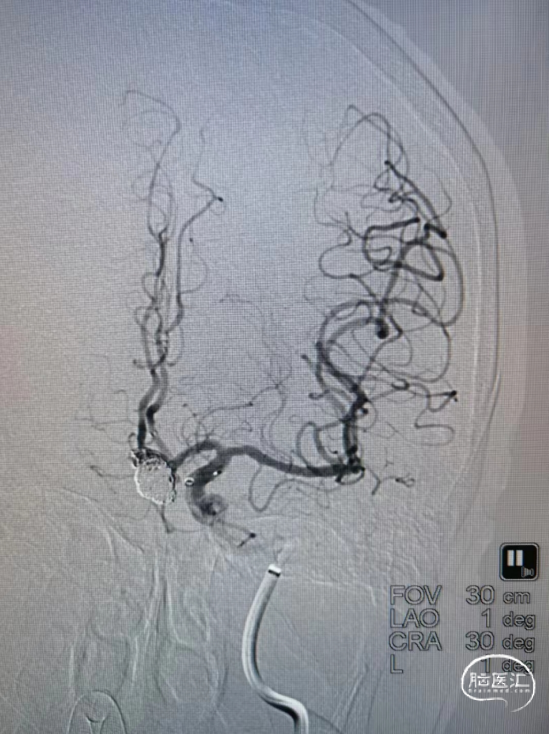

术后造影:弹簧圈致密填塞。

栓塞后造影:动脉瘤致密填塞。

遂小心撤出微导丝,再次复查造影,显影如前。以血管缝合器缝合右股动脉,常规加压包扎。术毕,全麻清醒如术前,安返病房。

复查造影。